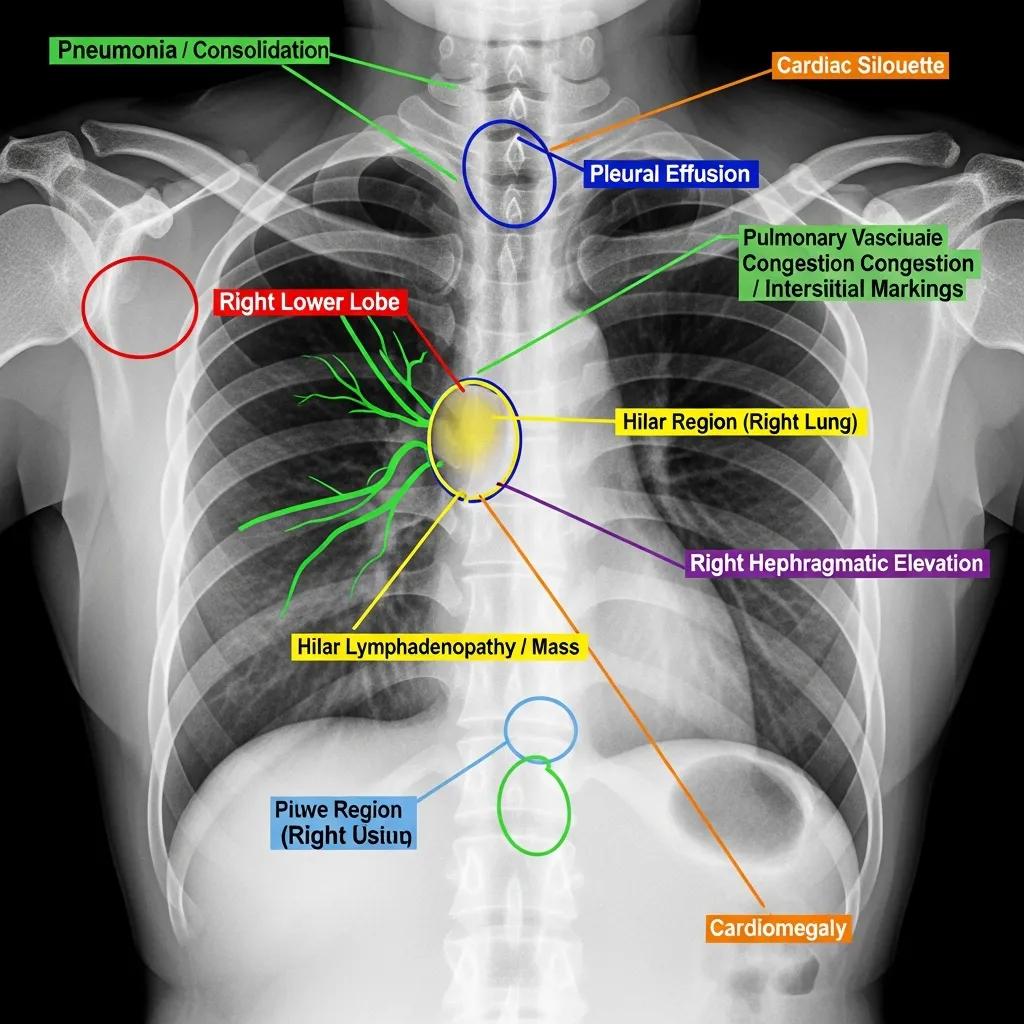

Chest X-Ray Findings: Normal Anatomy vs Common Abnormalities

Chest X-rays can reveal a variety of findings, ranging from normal anatomical structures to significant abnormalities. Common findings include:

- Lung Infections: Pneumonia or other infections may appear as areas of increased opacity in the lung fields.

- Fluid Accumulation: Conditions like pleural effusion can be identified by the presence of fluid in the pleural space.

- Tumors: Abnormal masses or nodules may indicate the presence of lung cancer or other malignancies.

- Heart Enlargement: Cardiomegaly can be assessed by examining the size and shape of the heart silhouette.

Understanding these findings is essential for healthcare providers to determine the appropriate course of action for patients.